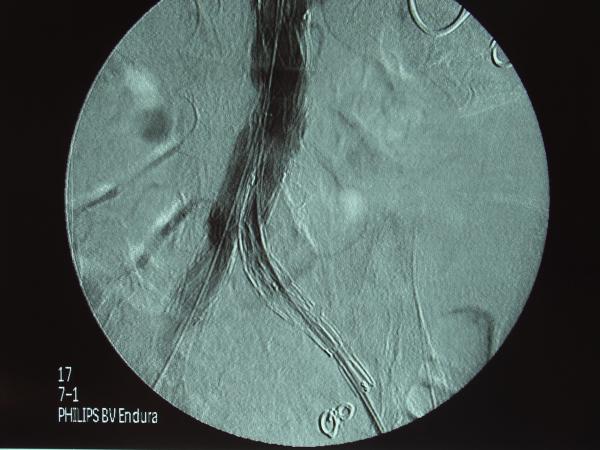

Ενδαγγειακή αποκατάσταση ανευρυσμάτων κοιλιακής αορτής

12ο Πανελλήνιο Συνέδριο Αγγειακής και Ενδαγγειακής Χειρουργικής

2010, Αθήνα